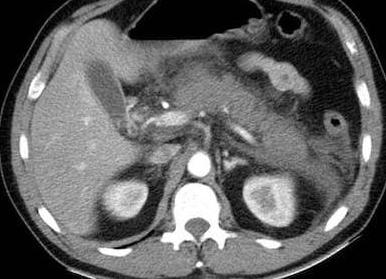

Если обнаруживается острая фаза панкреатита, то на компьютерной томографии врач наблюдает:

- очертание органа нечеткое;

- рядом с органом просматривается выделительная жидкость;

- ткани отечные, окружают поджелудочную железу;

- нет ячеистого строения, которое считается естественным явлением у здорового пациента.

При хроническом течении болезни поджелудочной возможно выявление кальциевого отложения.

Врачи отмечают высокую информативность данного исследовательского метода при диагностике панкреатита. Если обследование проводят пациенту с острым панкреатитом, врач увидит такую картину:

- нечеткие контуры поджелудочной железы;

- около железы врач видит экссудативную жидкость;

- отечность тканей, окружающих исследуемый орган;

- отсутствует ячеистая структура, которая является нормой для здорового, нормального органа.

Опасность такого прогрессирующего деструктивного процесса заключается в развитии панкреонекроза.

При хроническом панкреатите у обследуемого специалист может обнаружить отложения кальция. Это невозможно сделать посредством любого другого метода диагностики. У данной патологии имеются свои характерные признаки, которые заключаются в: